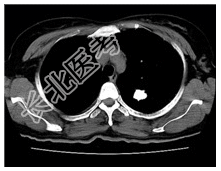

- [材料题] 患者,女性,51岁。体检发现左上肺高密度结节。查体:双肺呼吸音清,未闻及干湿性啰音。心脏无异常。行胸部CT平扫。

- 简答题1、患者的诊断及依据是什么?

- 简答题2、鉴别诊断有哪些?